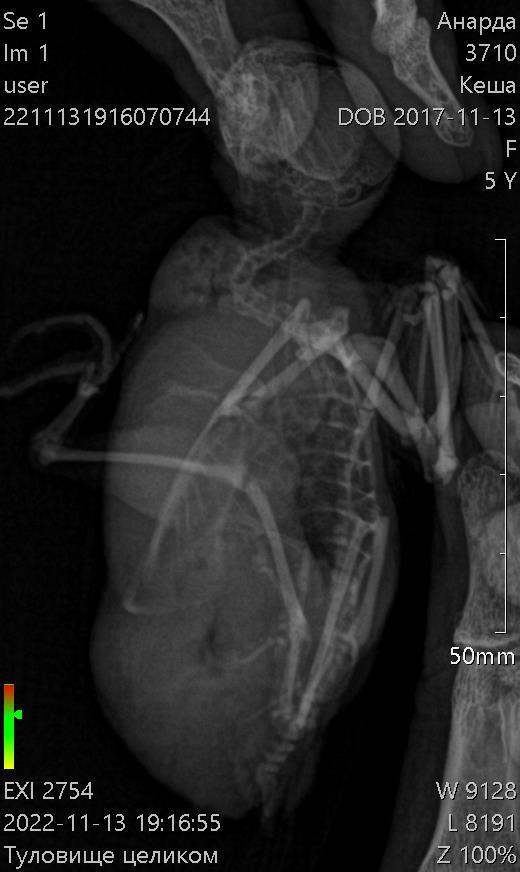

Здравствуйте! Пожалуйста, помогите моему волнистику. Больше месяца назад начались проблемы с калом. Начал какать редко и большими кучками. Сначала не придала значения, а потом у него начался сильнейший запор. Кеша перестал есть, пить, не мог вообще сходить в туалет. Орнитологов у нас нет в городе. После изучения информации на форумах, пропоила его биссептолом суспензией, кормили кашей и поили со шприца. В клюв капала вазелиновое масло. В еду линекс сыпала. Сейчас измельчаю карсил и добавляю в сухой корм. Ему стало легче, кал так и восстановился. Ходит большими кучками. Стал тяжело дышать, плохо и мало летать. На животе появилась опухоль. Сдали анализы на криптоспоридиоз и сальмонеллез- отрицательные. Сделали ренген. По результатам- проблемы с легкими и опухоль. Что делать? Умоляю, помогите!